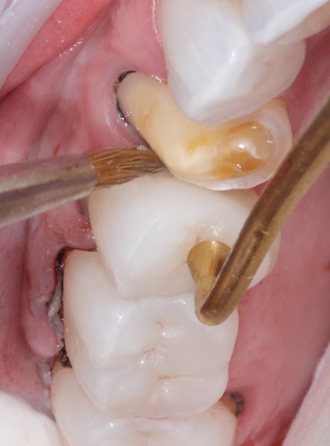

After a zirconia restoration is tried-in and cleaned, the intaglio surface should be airborne-particle abraded with alumina or silica-coated alumina particles (Figure 1). Some clinicians refer to this procedure as sandblasting or microetching. To air-abrade zirconia, a chairside microetcher using small particles ranging from 50 µm to 60 µm at a low pressure (ie, below 2 bar) is sufficient.7,9,11,12,27 The overall effect of pretreatment with alumina seems to be more important than the actual degree of surface roughening that it achieves, especially because of its ability to effectively decontaminate the bonding surfaces.27 As previously mentioned, the effects of air-particle abrasion on the flexural strength of zirconia have been discussed extensively, and most existing studies indicate that the use of particularly small particles actually provides a strengthening effect.28

(1.) Step A: airborne-particle abrasion of the intaglio surface of a zirconia restoration with 50-μm aluminum oxide at 1.5 bar using a chairside microetcher (Clinical photography courtesy of Marco Brindis, DDS).

Figure 1